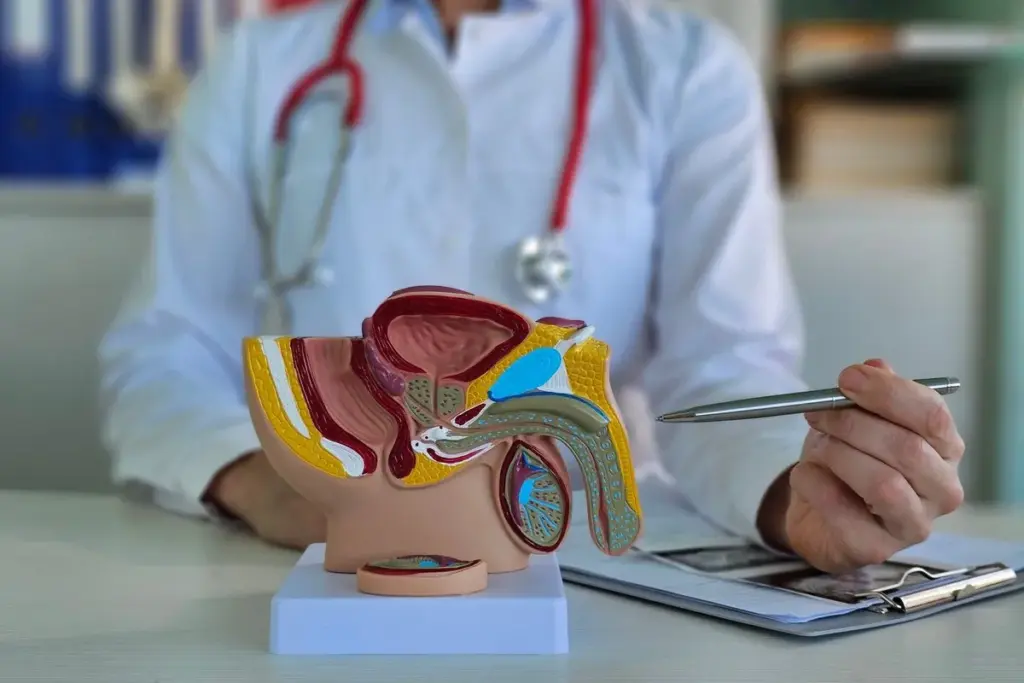

The testicles are key for making sperm and testosterone. Testicular cancer happens when these cells grow out of control, forming tumors. We’ll look at what this condition is, its types, and risk factors.

Diagnosis of Testicular Cancer

Diagnosing testicular cancer involves several steps. These include physical exams, imaging tests, and blood tests. Finding cancer early is key. Knowing about these steps helps spot cancer sooner.

Procedures for Diagnosis

A healthcare professional will first do a physical exam if a lump is found. This exam checks for swelling or tenderness. It also looks at overall health.

If cancer is thought to be present, more tests are done. These might include:

- Ultrasound imaging to see the testicles and find any issues.

- Blood tests to check tumor markers like alpha-fetoprotein (AFP), human chorionic gonadotropin (hCG), and lactate dehydrogenase (LDH).

- Surgical removal of the testicle (orchiectomy) for a clear diagnosis.

Imaging tests are key in finding testicular cancer. Ultrasound is often used. It can tell if a mass is solid or filled with fluid. This info is vital for treatment planning.

Computed tomography (CT) scans might also be used. They check if cancer has spread. This helps decide on the best treatment.